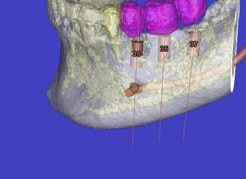

Auf Basis einer computertomografischen (CT-) Kieferaufnahme ist eine dreidimensionale Darstellung der Knochen möglich. Der Zahnarzt kann dann am Computerbildschirm die Knochenqualität (z. B. Knochendichte) beurteilen und die optimale Position der Implantate im Vorfeld planen. Durch Verwendung spezieller Röntgenschablonen lässt sich auch die erwünschte Zahnstellung in die Planung einbeziehen. Die Simulation der OP erlaubt, das zu erwartende Ergebnis mit größtmöglicher Sicherheit vorherzusagen und dem Patienten am Bildschirm zu veranschaulichen.

(siehe Bild 3 und 4).

Mit diesen gewonnenen Informationen und Planungen stellt der Zahnarzt interaktiv spezielle Bohrschablonen her. Diese ermöglichen eine exakte Positionierung der Implantate, so wie vorher am Computer geplant.

Weiterhin ist eine auf diese Weise geplante Operation für den Patienten weit weniger belastend. Denn die Freilegung des Knochens ist auf ein Minimum reduziert.